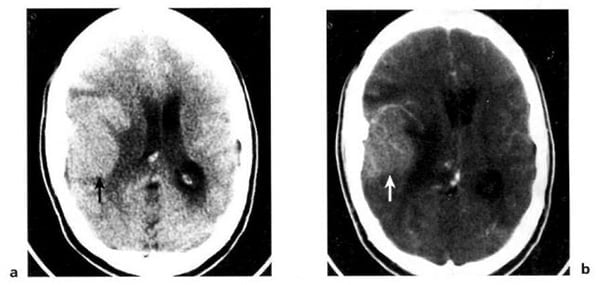

2.2. Nhồi máu não (Hình 1.40, 1.41)

Dấu hiệu XQCTĐT:

– Từ 12 đến 48 giờ: vùng mật độ thấp mơ hồ, giới hạn không rõ, hiệu ứng choán chỗ nhẹ (xóa rãnh vỏ, di lệch não thất nếu nhồi máu rộng). Không bắt chất cản quang thường xuyên. Xuất huyết xảy ra trong 5-10% với mật độ cao tự nhiên.

– Từ 48 đến 96 giờ: khối choán chỗ tăng dần. Vùng khu trú hình tam giác hoặc hình V, mật độ thấp, ảnh hưởng vỏ não và chất trắng dưới vỏ cho đến bề mặt não thất.

– Từ 4 đến 7 ngày: xuất hiện bắt chất cản quang dạng hồi não và có thể tồn tại trong 8 tuần. Nhồi máu mật độ thấp, phù bao quanh có mật độ thấp hơn.

– Từ 2 đến 8 tuần: hiệu ứng choán chỗ giảm dần, có thể còn bắt chất cản quang.

– Nhồi máu cũ: vùng mật độ thấp, giới hạn rõ, giãn nở não thất và rãnh vỏ lân cận. Hiếm đóng vôi.

Hình 1.40. Nhồi máu não. Dưới 24 giờ, ảnh hưởng toàn bộ vùng chi phối của động mạch cảnh trong bên trái. Tổn thương mật độ thấp, giới hạn không rõ đẩy lệch não thất bên.

Hình 1.41. Nhồi máu não ở tay sau của bao trong bên phải. Vài giờ sau khi xuất hiện triệu chứng của đột quỵ. XQCLĐT (a) âm tính. Sáu ngày sau (b), tổn thương mật độ thấp hiện rõ. Do kích thước nhỏ, hiệu ứng choán chỗ không đáng kể.